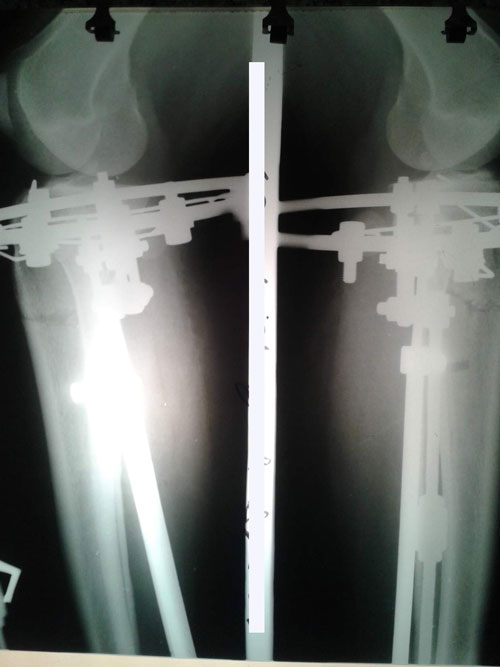

Дата операции 17.11.2015г.

Дата снятия аппаратов 10.02.2016г.

Срок лечения 85 дней.